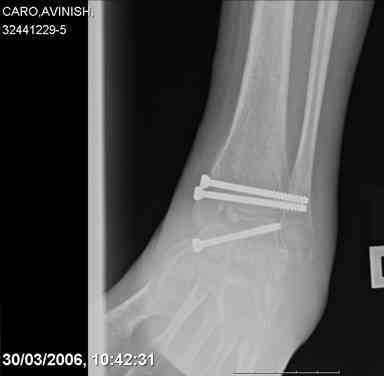

ya by popytalsya sobrat talus anatomichno,seichas pozdno operirovat iz za oteka,po etomy distrakziya apparatom budet optmalna.Posyalu vam podobyai moi sluchai.

14 years old girl

Fall from height ( 3rd floor)